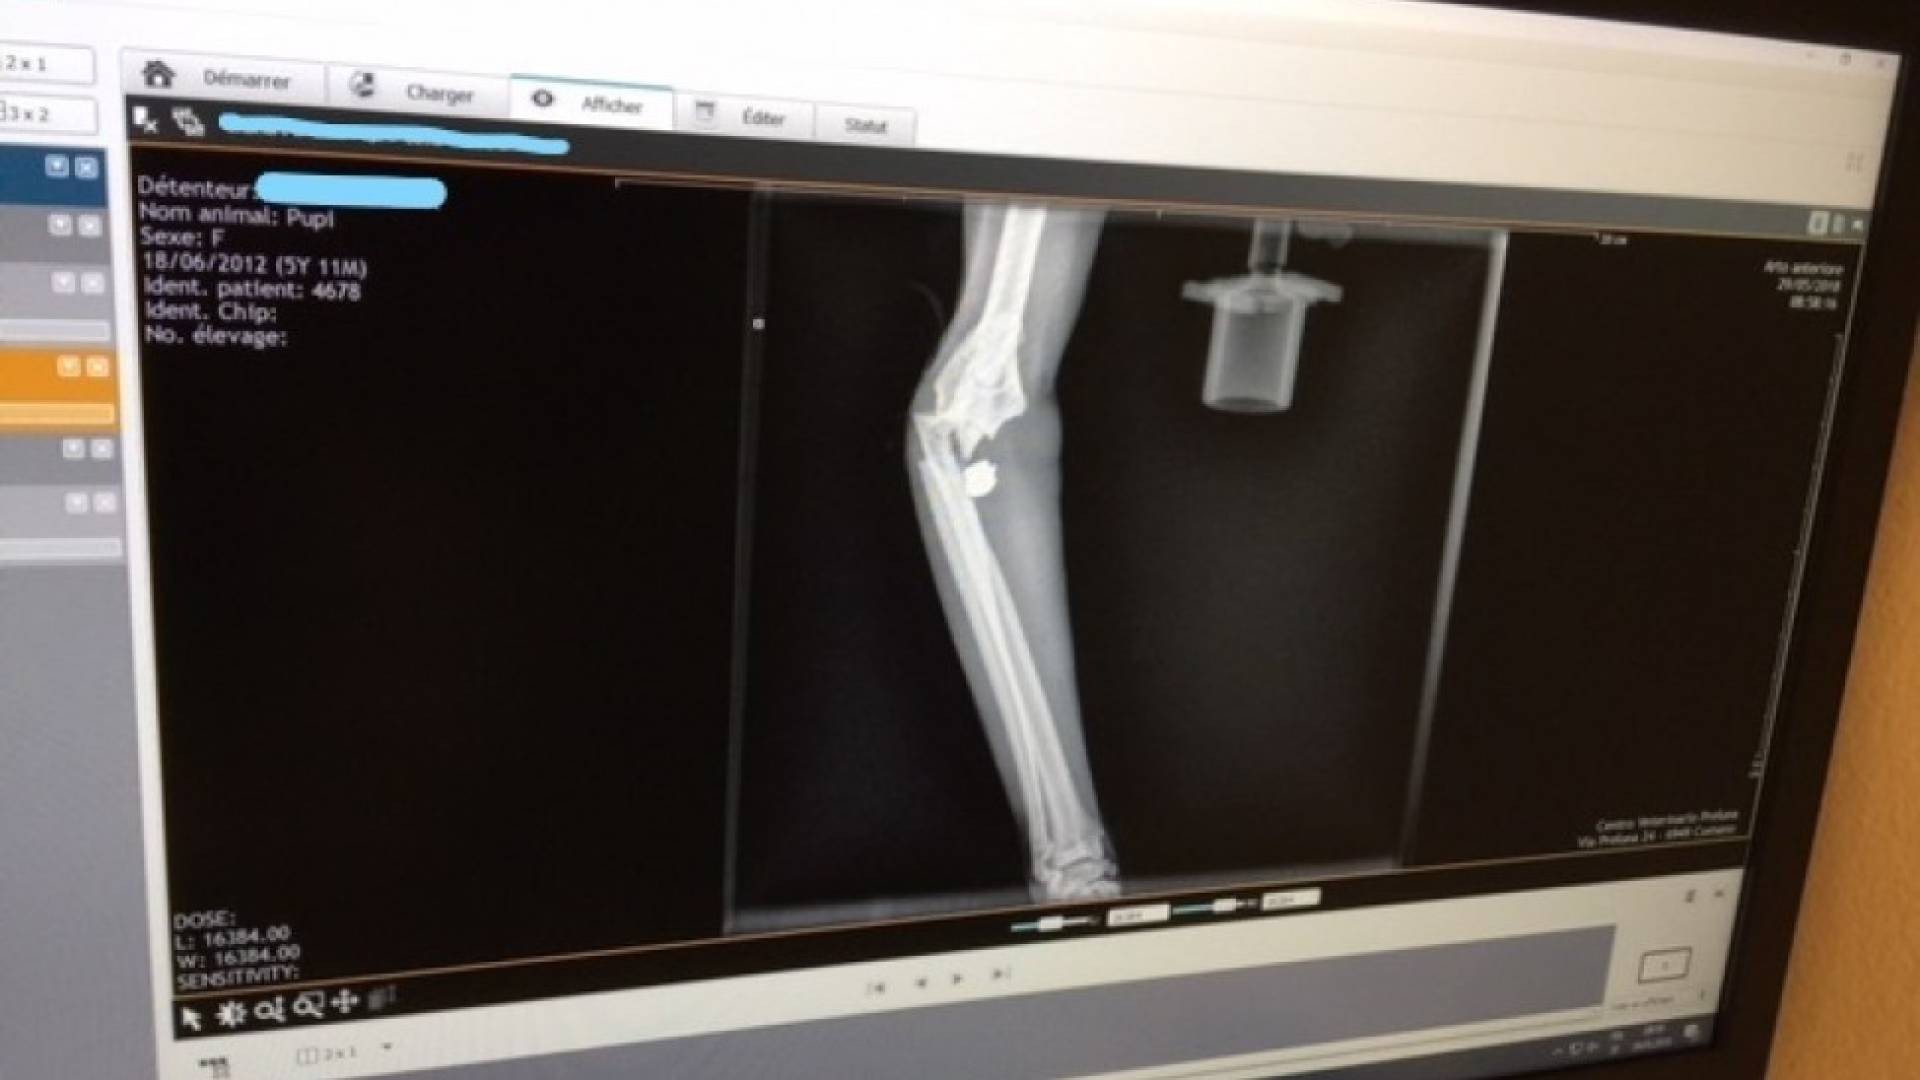

"Accorsi a vedere cosa avesse questa povera bestiola - scrivono i proprietari - ci siamo accorti che aveva una zampa sollevata e abbiamo intuito che era rotta. A fatica siamo riusciti a prenderla poiché cercava riparo sotto il letto uscendo solo con la testolina e guardandomi con quei suoi due occhioni che mi chiedevano aiuto. Subito dopo essere riusciti a prenderla l'abbiamo portata dal veterinario per farla visitare e dalla radiografia eseguita è stato evidenziato quello che si temeva. Il fatto sconcertante è l'aver verificato che la ferita era dovuta ad un piombino sparato da una pistola o da un fucile ad aria compressa, conficcato vicino alle sue ossicine. La gattina è morta poco dopo, a causa di una embolia dovuta alla lesione".